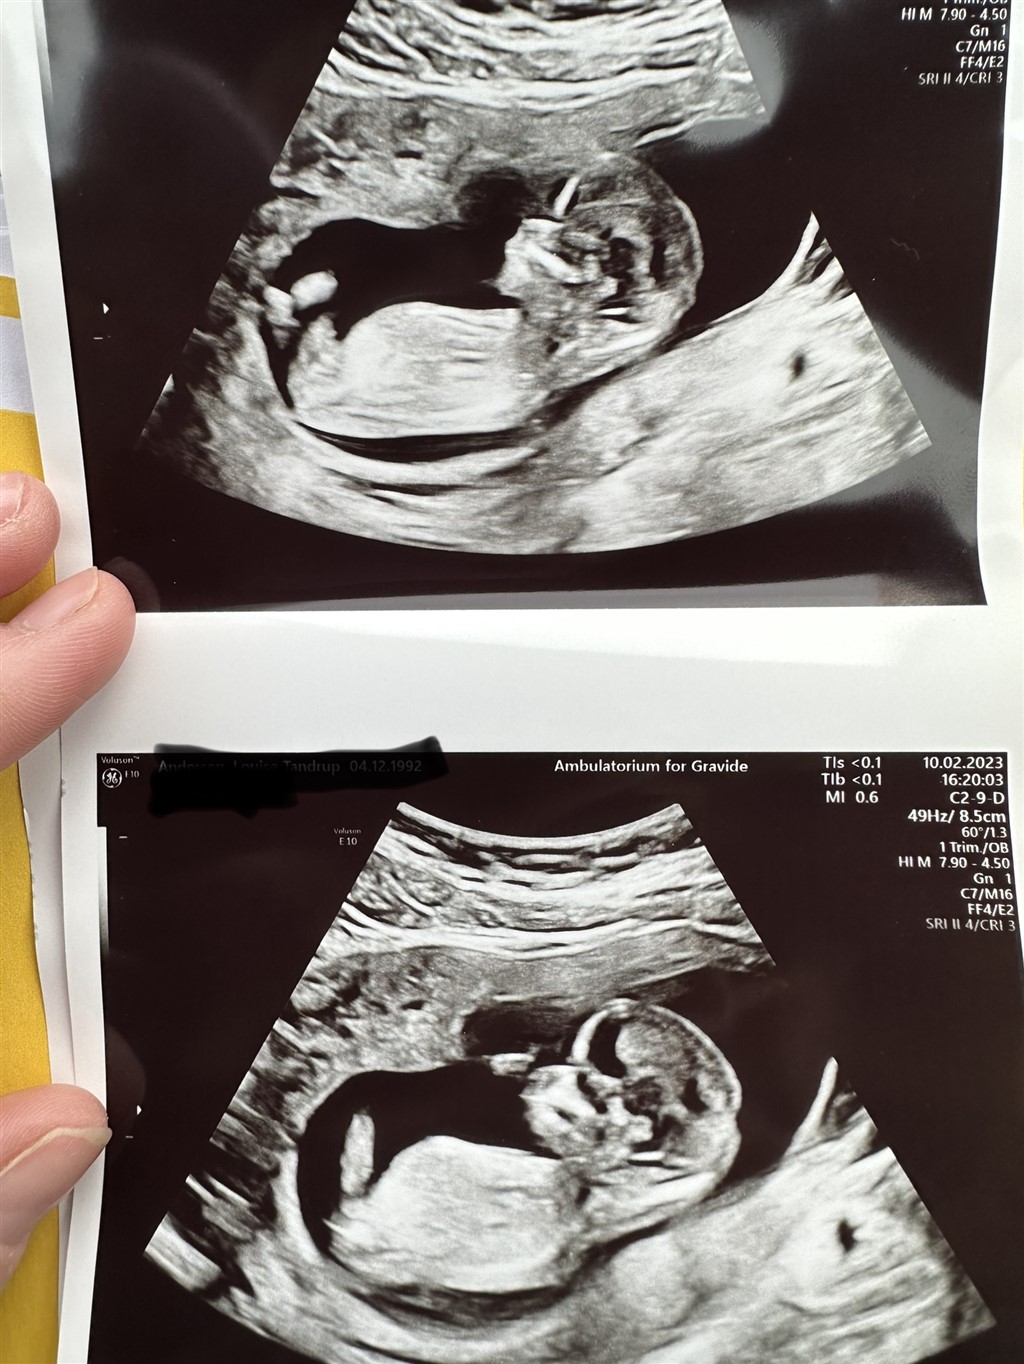

Var 13+1 da billederne blev taget.

Er der nogle der vil hjælpe med at prøve at gætte kønnet?

Kan man overhovedet se nub på disse billeder?

Mit umiddelbare bud er en dreng